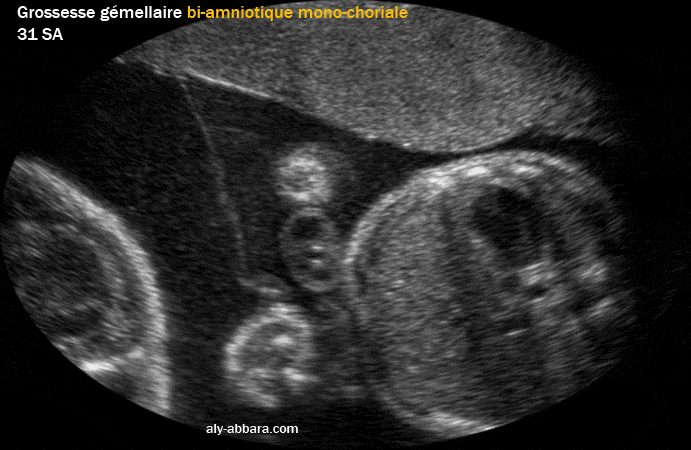

• Image échographique montrant le type de placentation d'une grossesse gémellaire mono-choriale bi-amniotique (vrais jumeaux).

• Le raccordement de la membrane inter-ovulaire au niveau de la plaque choriale prend l'aspect de " T " ; ce raccordement est connu sous le nom du signe de T qui témoigne de la monochorionicité.

• La cloison inter-ovulaire est formée de deux amnios seulement (sans chorion).

• Cette forme de placentation (mon-choriale ; bi-amniotique) se voit dans 70 % des grossesses gémellaires monozygotes (vrais jumeaux).